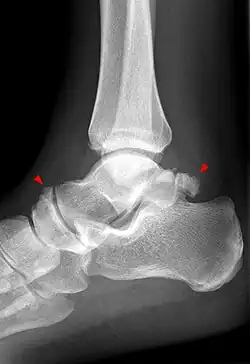

Anatomia radiologică a talusului

Talusul se vizualizează atât în incidența de față a gleznei[83] sau piciorului,[84] cât și pe cea de profil a gleznei sau piciorului, precum și în incidența oblică pentru articulația talo-calcaneeană.[83][85]

Pe radiografia de față a gleznei se identifică alături de talus și interlinia articulară a gleznei (tibio-fibulo-talară), iar pe cea de profil alături de talus (cu capul, colul și procesul posterior), spațiul articular talo-crural, articulația talo-naviculară,[83] precum și articulația talo-calcaneeană.[84] Tot pe radiografia de profil, se poate observa arhitectura regiunii, remarcându-se continuitatea traveelor osoase din tibie spre talus și calcaneu, iar de aici spre restul plantei.[84]